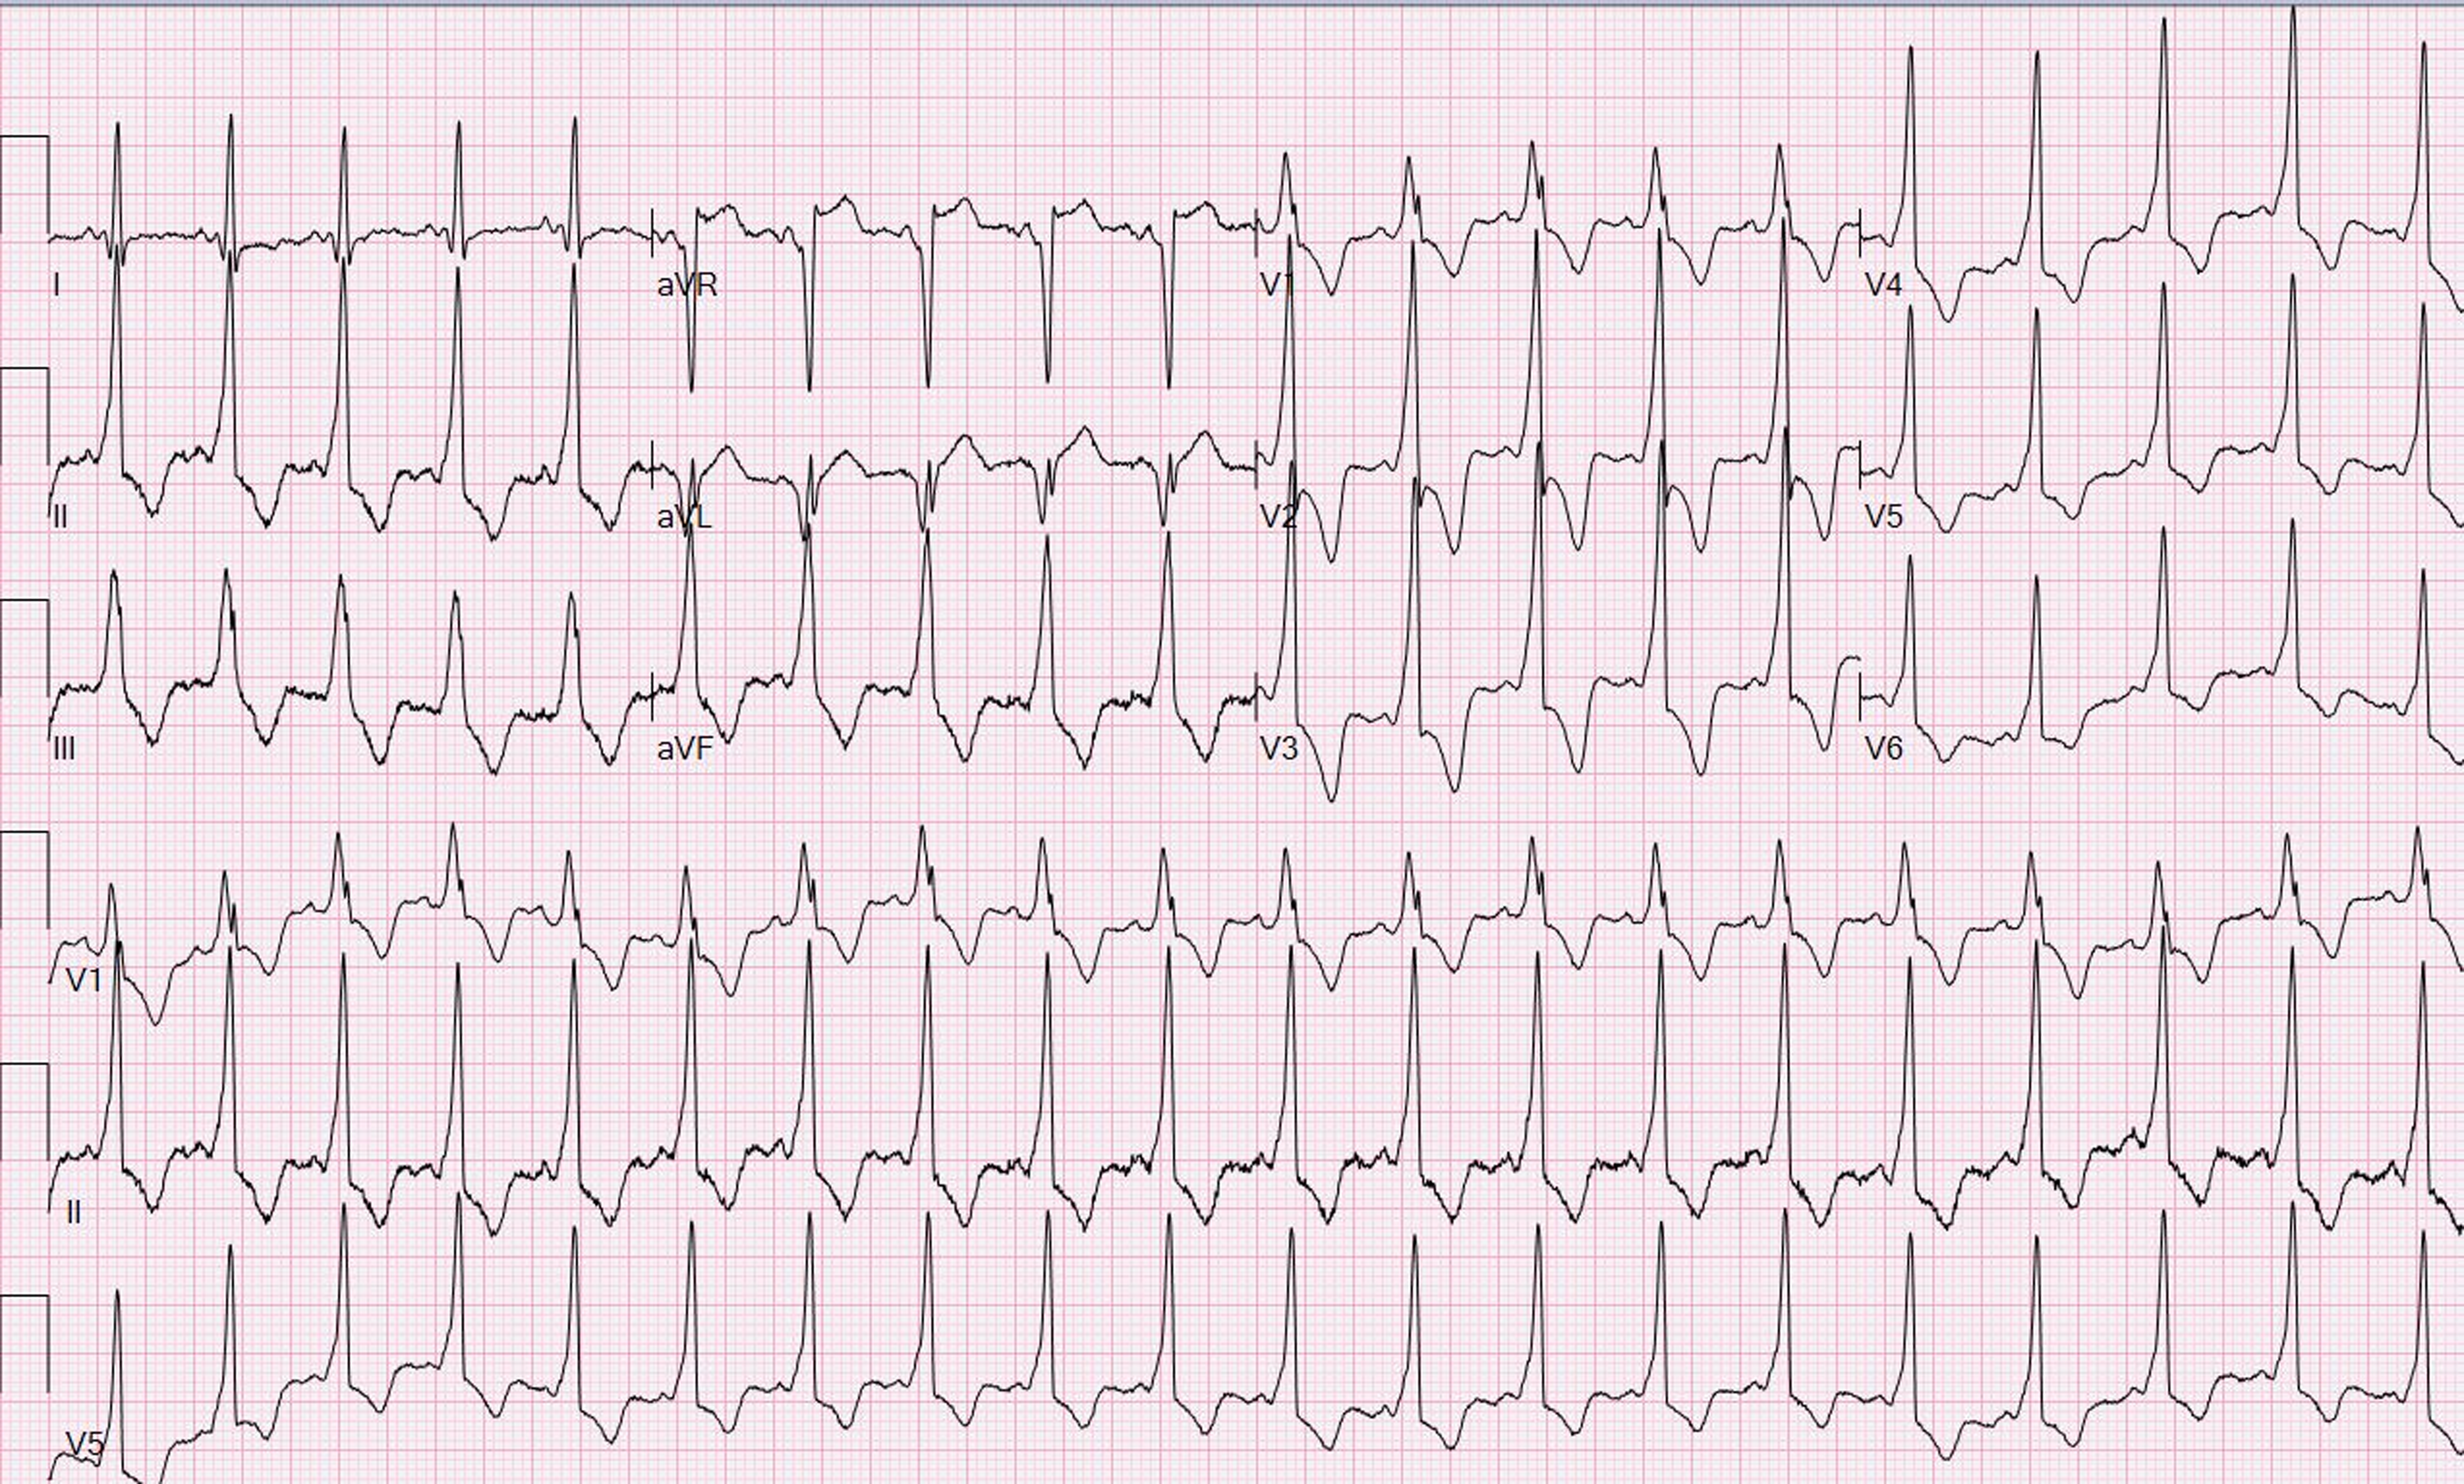

A 17-year-old girl presented with palpitations and Wolff–Parkinson–White pattern on electrocardiogram (Figure 1). Her echocardiogram was suggestive of left ventricular non-compaction with preserved ejection fraction (Figure 2A, Video 1). This was confirmed on cardiac magnetic resonance imaging per criteria proposed by Petersen et al (Figure 2B, Video 2).Reference Petersen, Selvanayagam and Wiesmann7 She underwent an exercise stress test during which pre-excitation persisted at a peak heart rate of 171 beats per minute suggesting a possible high-risk pathway. She subsequently underwent an electrophysiology study during which orthodromic reentrant tachycardia was induced (cycle length of 460 msec) with programmed atrial stimulation. On decremental atrial pacing, the accessory pathway block cycle length was < 200 milliseconds and the shortest preexcited RR interval during atrial fibrillation measured 174 msec (Figure 3), findings which confirmed the pathway to be high risk. The episode of atrial fibrillation resulted in haemodynamic instability and required immediate cardioversion. Mapping was therefore only performed during pre-excited sinus rhythm. Earliest ventricular activation during sinus rhythm was noted over a broad area in mid coronary sinus and superolateral mitral annulus. However, application of radiofrequency energy at these sites was not successful in eliminating pre-excitation (Figure 4). She was started on sotalol until she underwent another EP study a month later. This time, the earliest ventricular activation during sinus rhythm was recorded over a broad area located from 2 to 4 o’clock along the mitral valve annulus. Empiric radiofrequency ablation was performed at the site. Orthodromic reentrant tachycardia was induced following initial ablations (Figure 5A), but no tachycardia could be induced following consolidation of the site. No ventriculoatrial conduction was noted following consolidation. Anterograde accessory pathway conduction, however, persisted, but antegrade pathway block occurred at an atrial pacing cycle length of 450 msec suggesting that the pathway had been modified. Eighteen months following the second ablation, the patient presented to the emergency department in supraventricular tachycardia, which was terminated with adenosine (Figure 5B). She is currently treated with flecainide 75 mg twice daily and is doing well.

Figure 1. 12-lead electrocardiogram shows ventricular pre-excitation with left anterior pathway location.